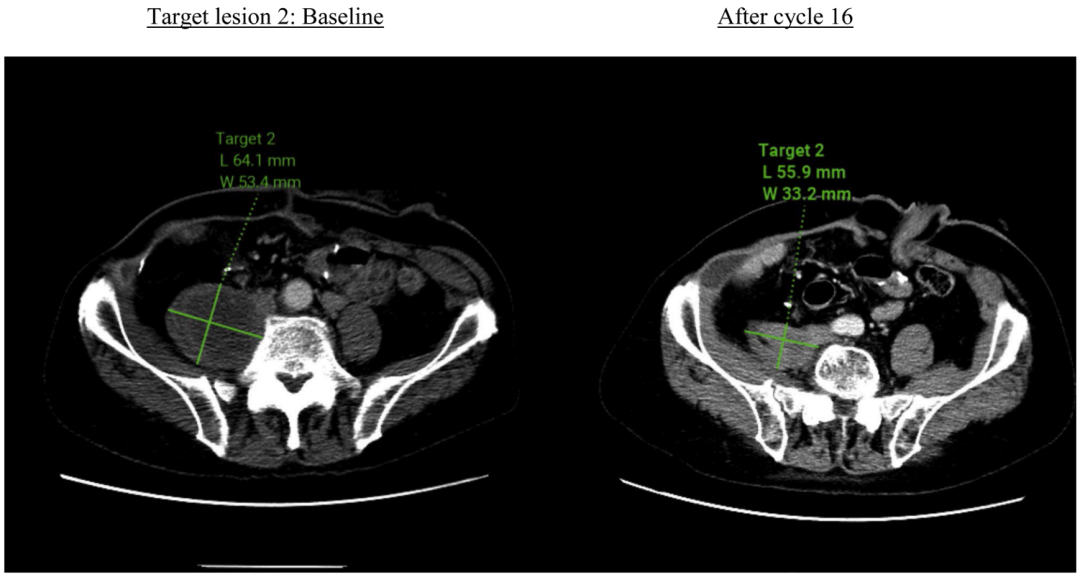

根据RECIST 1.1标准评价,该患者的最佳疗效评价为部分缓解(PR)。影像学数据显示,目标病灶的体积较基线水平缩小了31.7%。

图1 靶病灶退缩情况